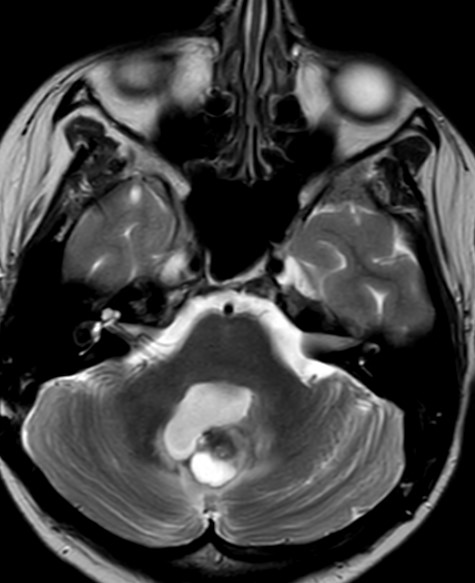

MRT Kopf – was sieht man?

Eine Kopf MRT liefert Ärzte und Radiologen detaillierte Bilder. Zu sehen sind das Gehirn, Schädelknochen, Blutgefäße und anderer umgebende Gewebe im Kopfbereich.

- Tumore und Zysten: Die MRT Kopf kann sowohl gutartige als auch bösartige Tumore im Gehirn erkennen. Sie kann auch bei der Identifizierung von Zysten und anderen strukturellen Anomalien helfen.

- Schlaganfälle und Blutungen: Auf den MRT-Bildern vom Kopf sind frische Schlaganfälle, Hirnblutungen und andere vaskuläre Probleme im Gehirn zu erkennen.

- Entzündungen und Infektionen: Entzündliche Zustände im Gehirn, wie Enzephalitis oder Abszesse, können durch die MRT Kopf Untersuchung identifiziert werden.

- Degenerative Erkrankungen: Die Kopf MRT kann bei der Diagnose degenerativer Erkrankungen wie Alzheimer oder Multipler Sklerose (Link) helfen, indem sie Veränderungen im Gehirngewebe zeigt.